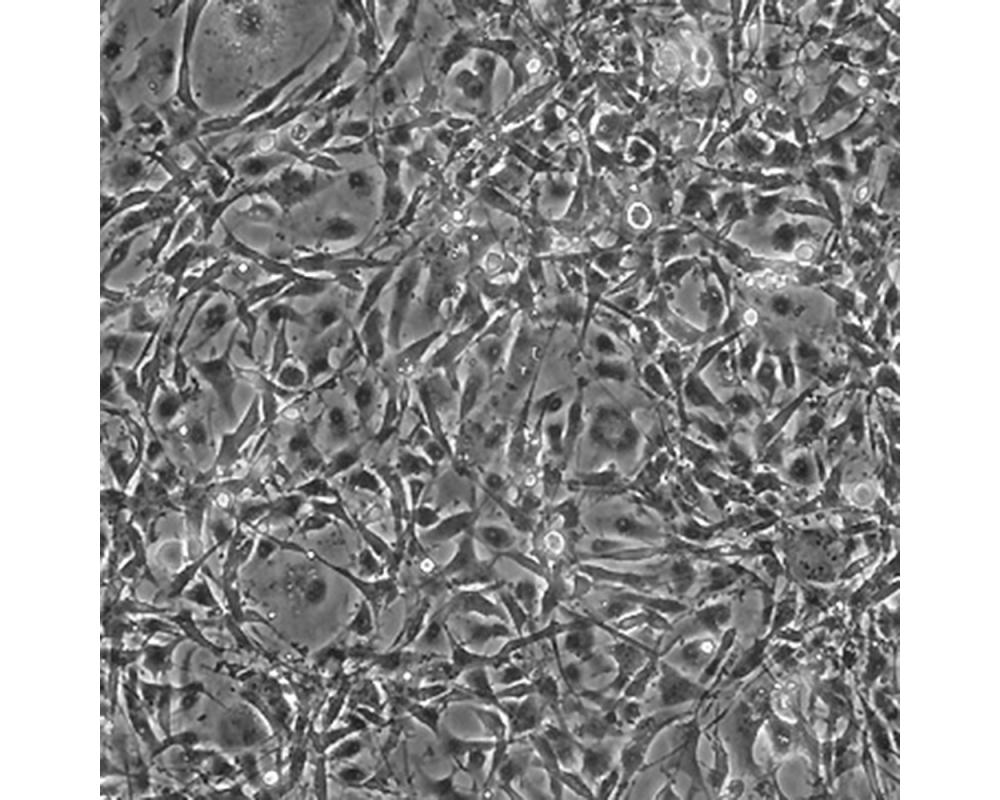

U-118 MG

中文名稱 人腦星形膠質(zhì)母細(xì)胞瘤

組織來源 星形膠質(zhì)母細(xì)胞瘤;男性

生長特性 adherent

培養(yǎng)基 DMEM+10% FBS+1% P/S

形態(tài)特征 mixed

傳代方法 1:3-1:6

細(xì)胞描述 注意: 據(jù)報(bào)道來自不同個(gè)體的膠質(zhì)母細(xì)胞瘤細(xì)胞株U-118 MG (HTB-15) 和 U-138 MG (HTB-16)有著一致的VNTR和相近的STR模式。 U-118 MG 和 U-138 MG細(xì)胞遺傳學(xué)上很相似并有至少六個(gè)衍生標(biāo)記染色體。 這是1966年至1969年間J. Ponten和同事從惡性神經(jīng)膠質(zhì)瘤中構(gòu)建的細(xì)胞株中的一株(其它包括ATCC HTB-14和 ATCC HTB-16 and ATCC HTB-17)。 1987年用BM-Cycline培養(yǎng)6周去除了支原體污染。